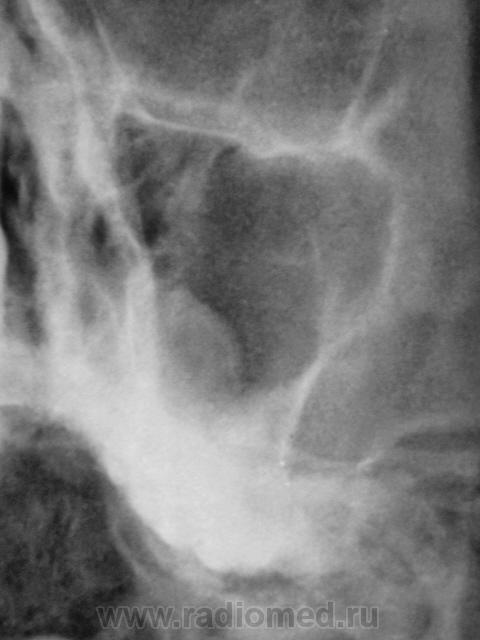

Пациент первый.

Киста, или что другое?

Больше похоже на кисту. Четкий округлый контур с характерным месторасположением. Хотя может и не так все просто)

да,  похоже на кисту, но справа снижена пневматизация верхнечел.пазухи за счет умеренного отека, я бы кисту слева под вопросом написала и направила на контроль

---------------------------------------------------------------------------------------------------------------------------------------------------------------------------------+1: как вариант,  можно предположить, что киста одонтогенного происхождения.